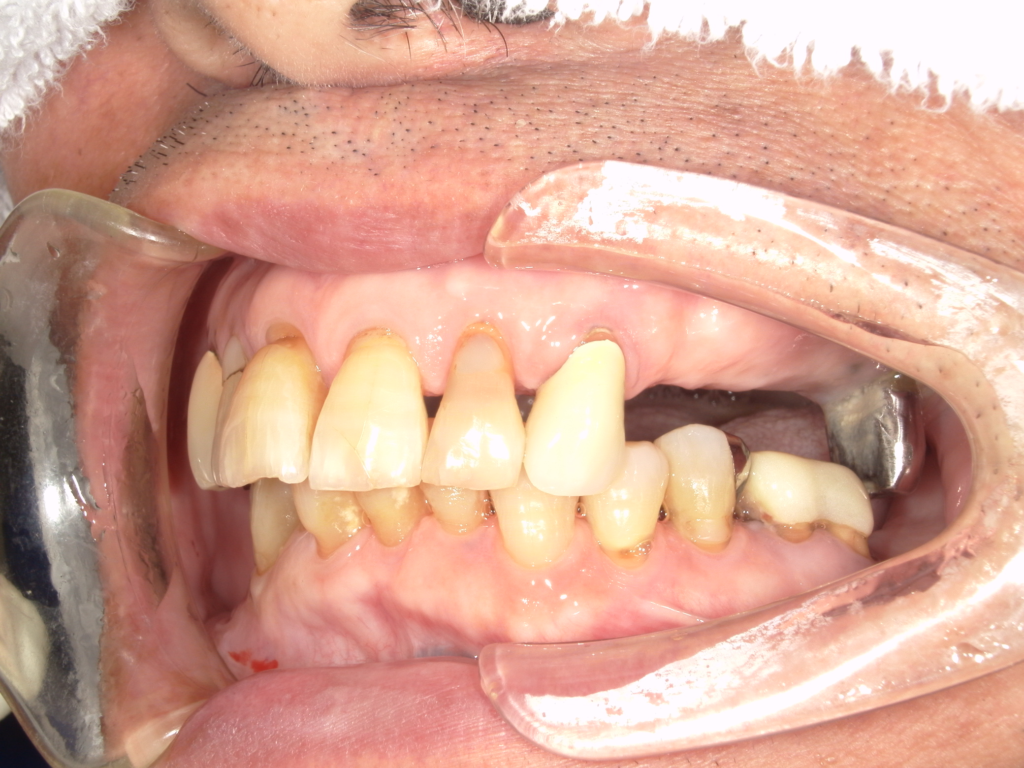

Y様インプラント実例 #44

左の上下の奥歯をインプラントで治療しています。

左下の奥歯は歯を抜くのと同時にインプラントの埋め込みを行っています。

被せものは上下、セラミックスで作っています。

治療前

治療後